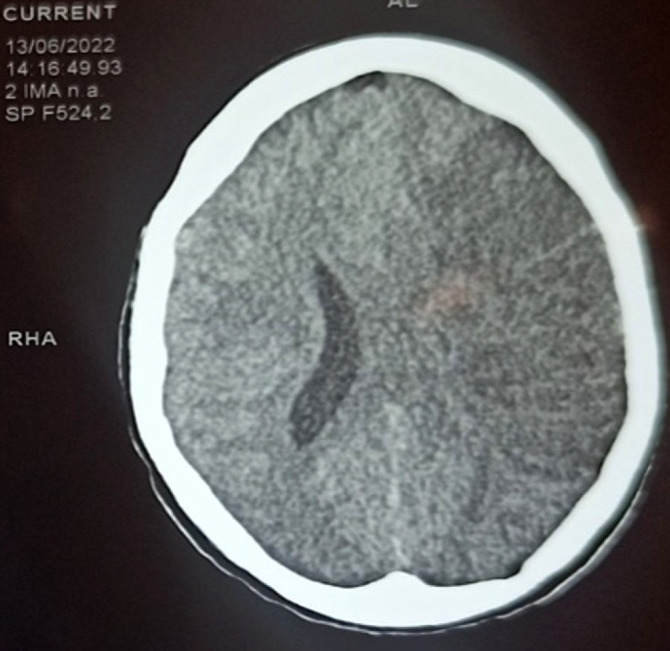

Extended-spectrum beta-lactamase-secreting Enterobacteriaceae (ESBL-E) infections constitute a real global public health problem, particularly in sub-Saharan Africa. We report here two cases of ESBL-E meningoencephalitis in young female patients occurring in a gestational context observed at the infectious and tropical diseases department of the Point G university hospital in Bamako. The first woman, who recently had an abortion, was being treated with ceftriaxone when she was admitted for meningeal syndrome and pyramidal syndrome associated with brain damage. Escherichia coli resistant to penicillins and cephalosporins was isolated from cerebrospinal fluid (CSF), blood and a purulent genital swab. She recovered under meropenem treatment for 21 days, with few sequelae.The second had given birth in the weeks prior to the onset of generalized infection. She was admitted for meningeal syndrome and pyramidal syndrome associated with several cerebral lesions disclosed by the CT scan. Multidrug-resistant E. coli was isolated from CSF and genital purulent sample. She recovered (with sequelae) under treatment with meropenem for 21 days. These two observations show that female genital infections (postpartum or post abortum) with E. coli can cause forms as serious as meningoencephalitis, in addition to the abortion they cause. ESBL-E -producing strains may be involved and represent a major therapeutic challenge. Better infection prevention and control would prevent multi-drug-resistant infections and their spread. Regulating the use of carbapenems and other antibiotics still effective against multi-resistant bacterial strains within the framework of global health (one health) would avert an incurable pandemic of highly resistant and emerging bacteria (HRB).